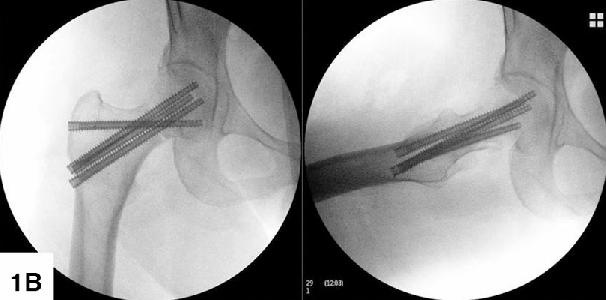

2. 全螺纹钉交叉固定 (FTS / Crossed Screw) —— “长度维持派”